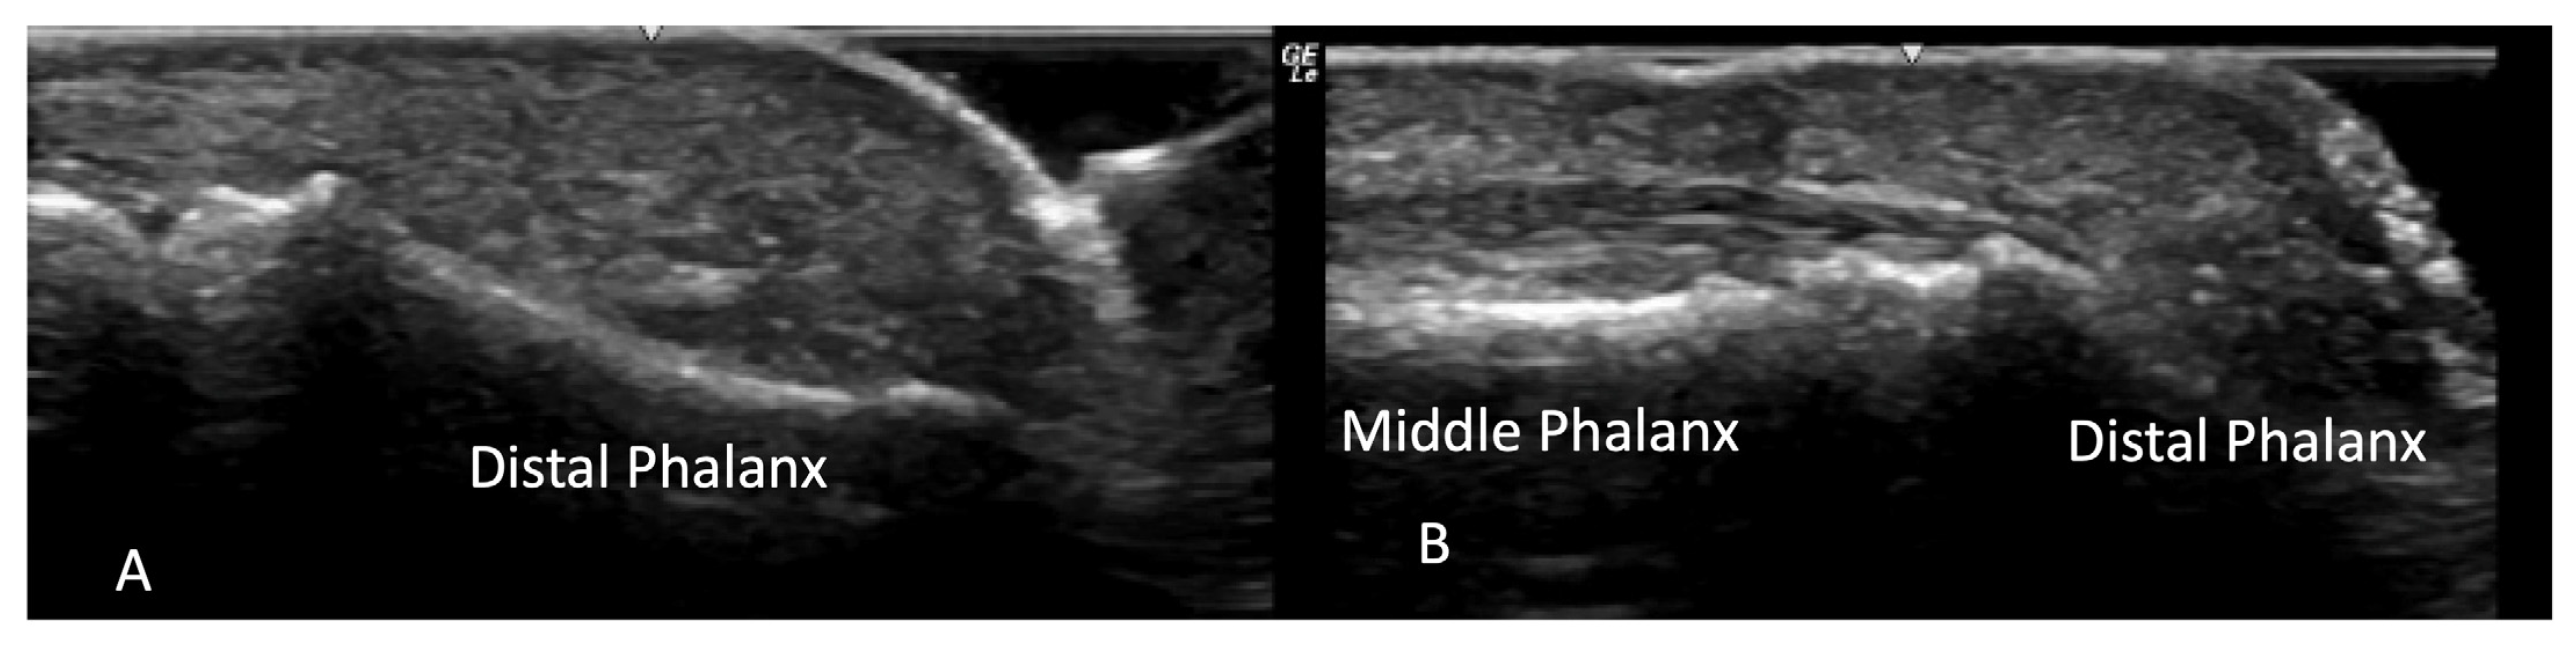

4.1. Evaluation of the Fingers

4.1.1. Dorsal Aspect

4.1.2. Volar Aspect